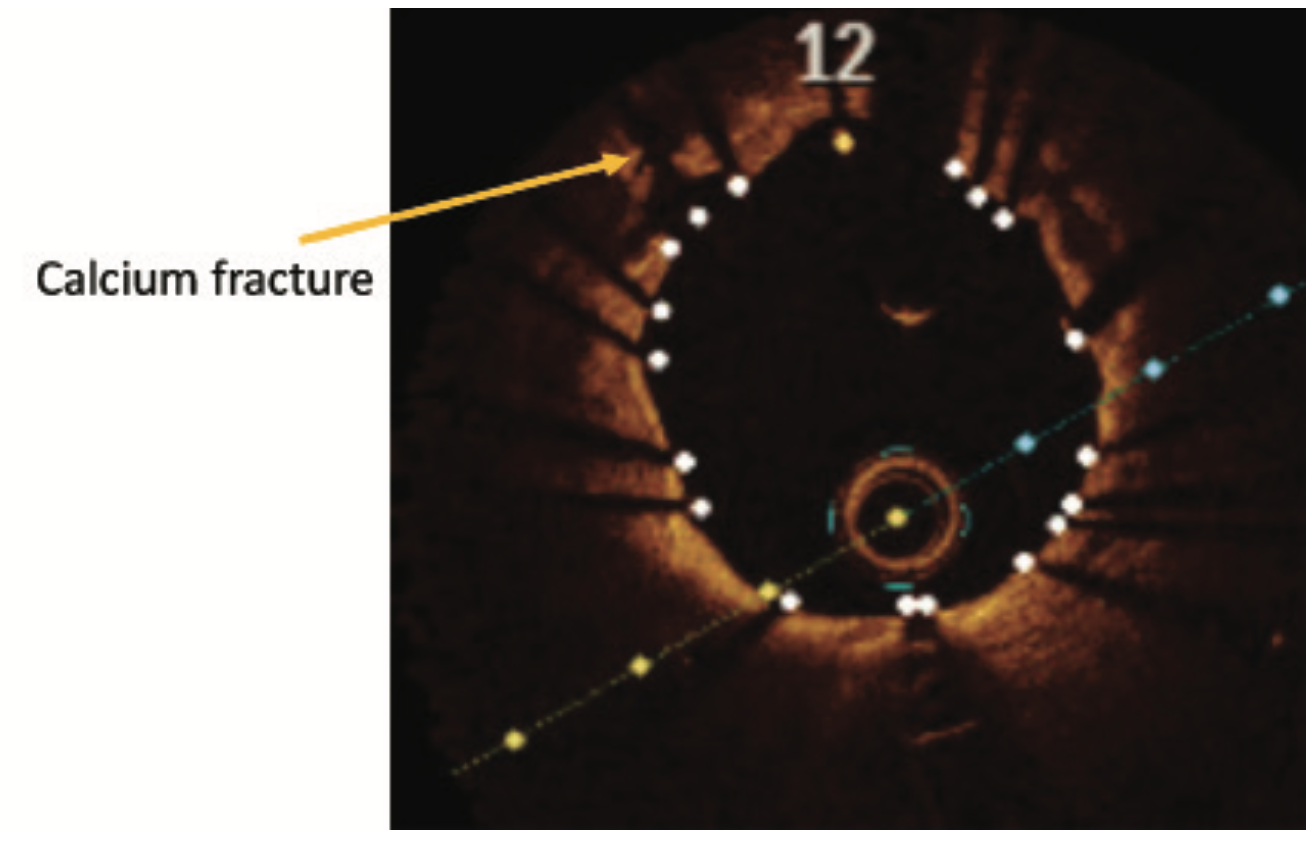

Intravascular lithotripsy (IVL) has been shown to be both safe and effective in the treatment of calcified coronary artery disease, with low rates of device-related adverse events, as shown in the DISRUPT CAD study series.3-6 Certainly, any device that may assuage operator concerns regarding complications when treating complex lesions could translate to an increase in use of calcium modification where indicated. Since we know that inadequate lesion preparation may lead to higher rates of in-stent restenosis and stent thrombosis, it follows that IVL could help lower suboptimal PCI rates in both men and women.

Small retrospective studies have suggested that women may be at an increased risk for procedural complications after atherectomy. Procedural complications are often related to vascular injury during plaque modification. As post-menopausal women have been shown to have increased arterial stiffness, less vessel compliance, and increased vascular fragility, it is not surprising that these factors, in conjunction with smaller coronary artery size, could lead to higher rates of coronary perforation and dissection during treatment of calcified plaque. The sex-specific analysis of the DISRUPT CAD series of studies presented at SCAI 2022 demonstrated that there was no difference in angiographic complications, successful stent delivery, and 30-day adverse cardiovascular events between men and women.7 These are certainly reassuring data, which suggest that the possible safety signals seen in women treated with atherectomy may not be present with IVL.